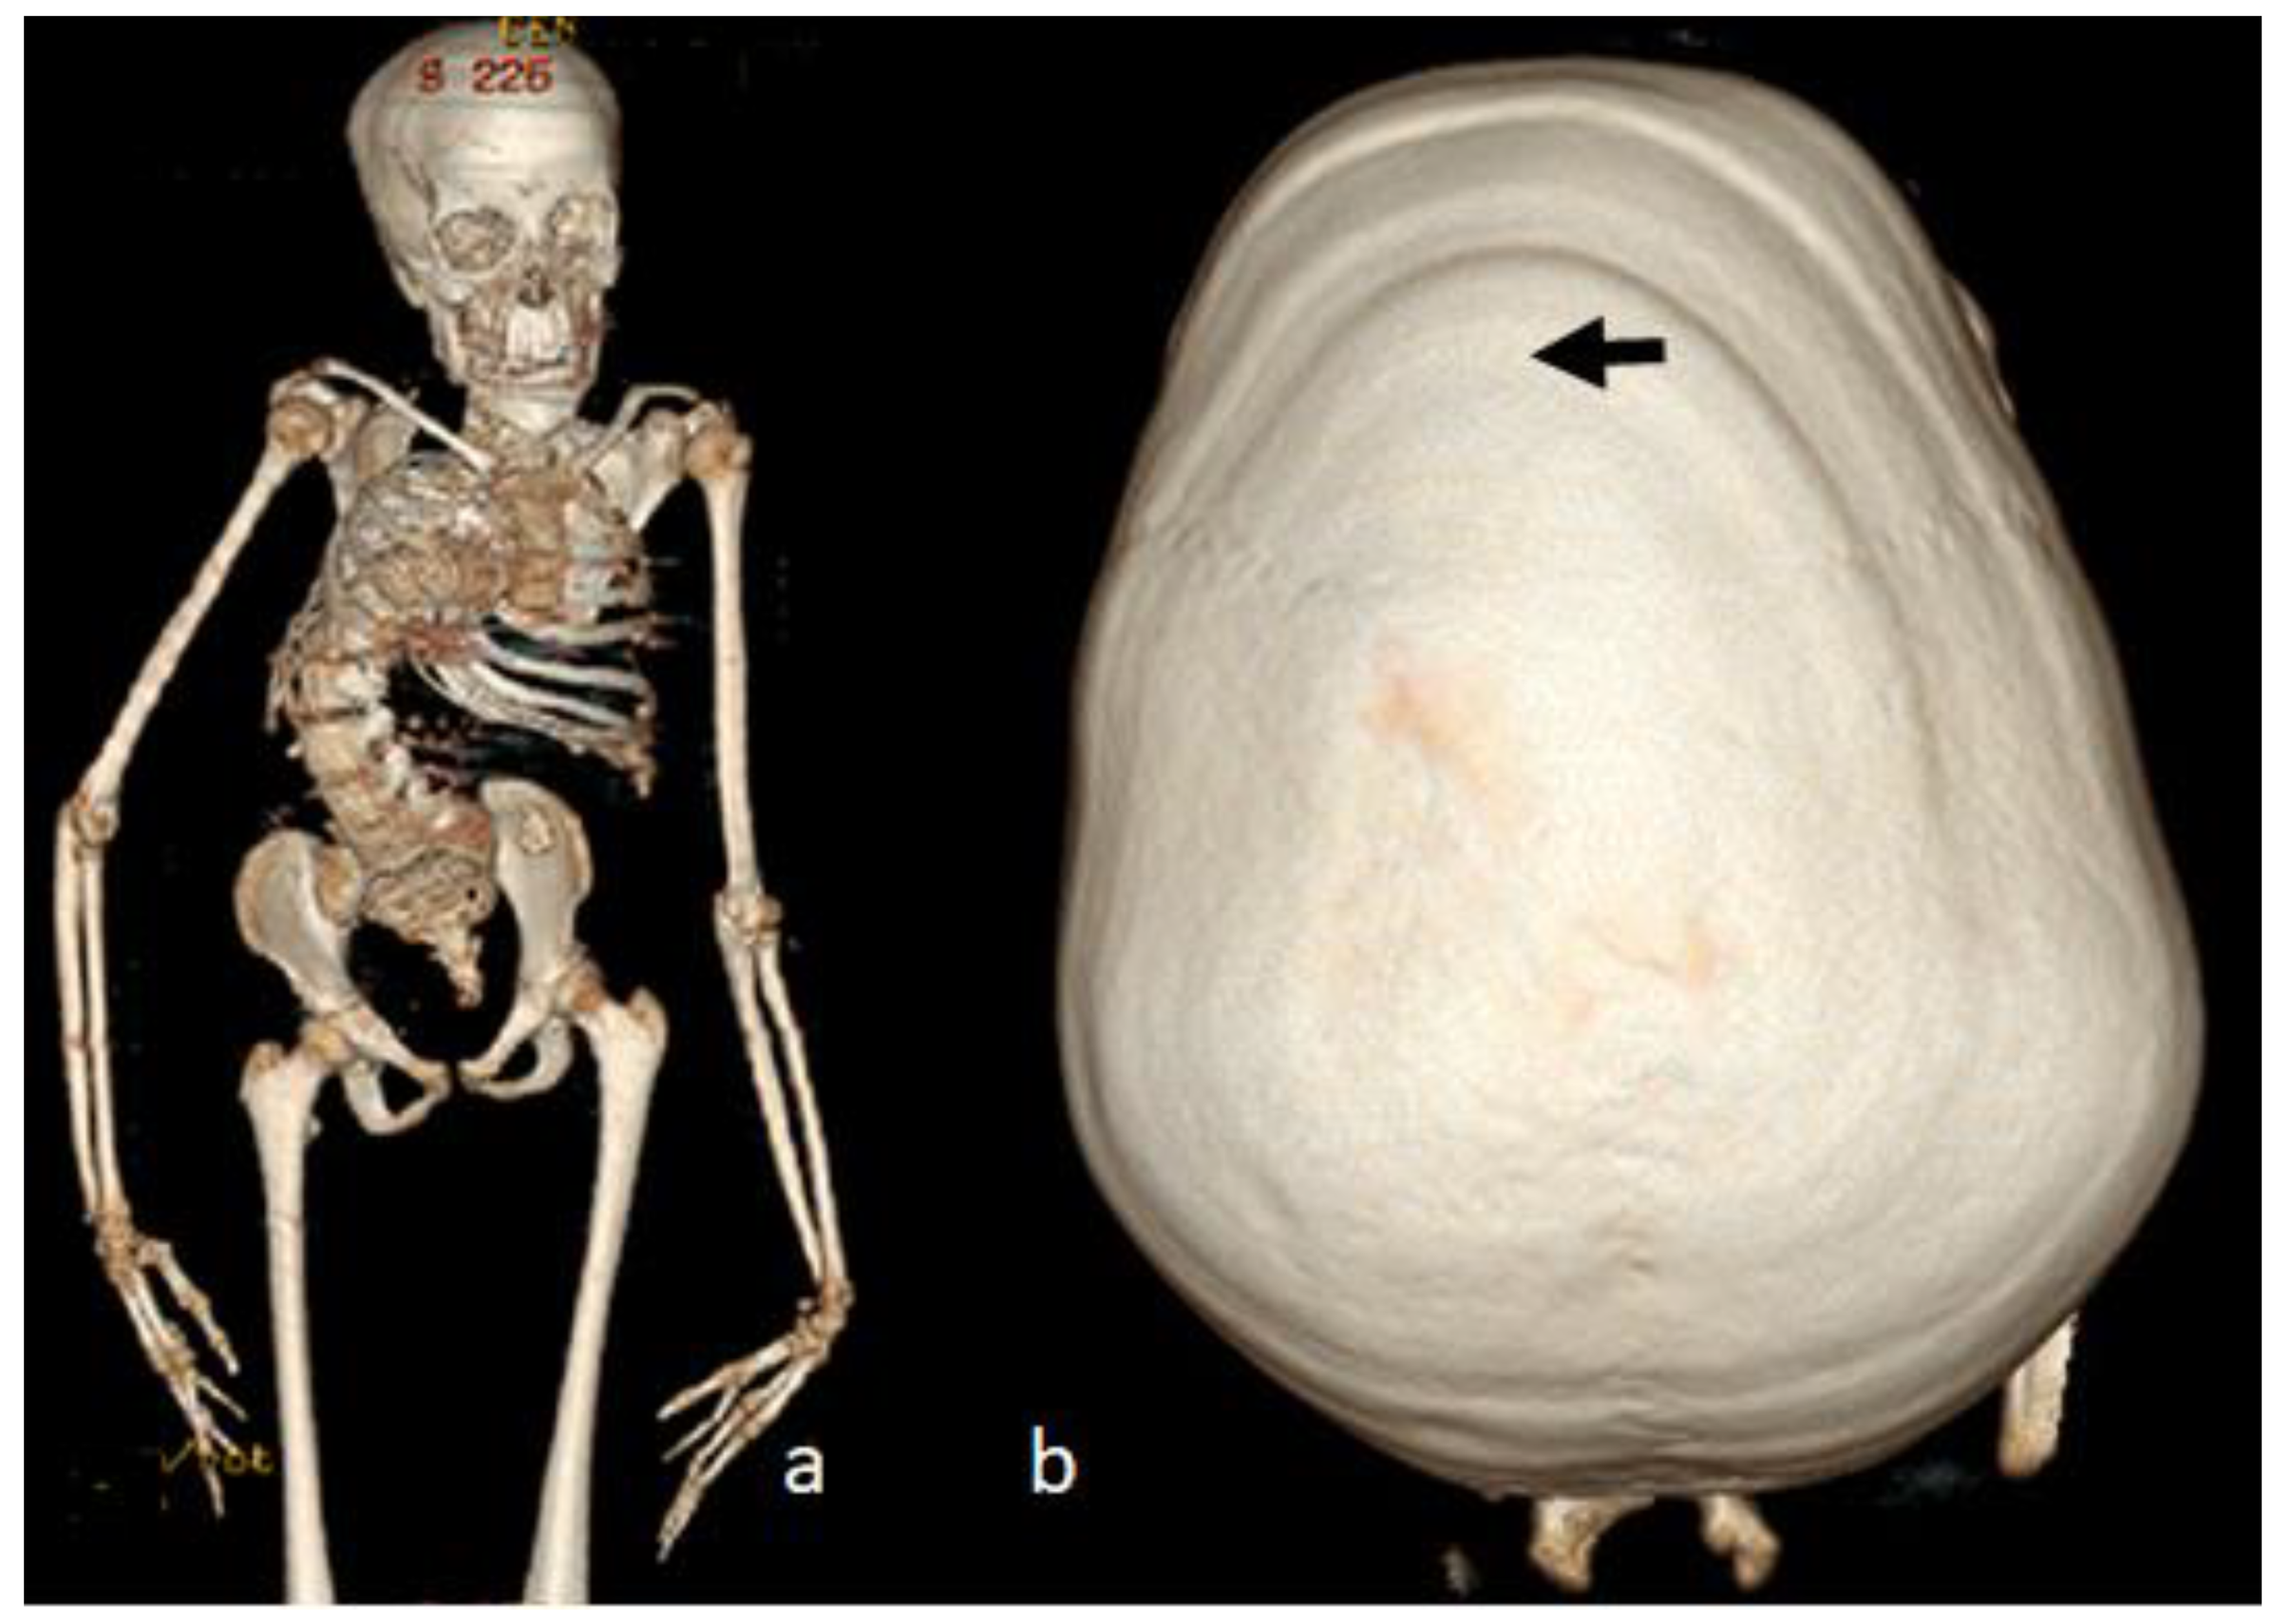

For this syndrome, we clinically investigated two unrelated affected boys. The first was a one-month-old boy presenting with multiple contractures who was falsely diagnosed in other institutes as having positional plagiocephaly associated with idiopathic multiple contractures. A clinical examination at the age of one month showed growth deficiency (-2SD) and OFC (around the 75th percentile). Clinically, he manifested an abnormal craniofacial contour with prominent sloping of the frontal area. The helices were over-folded. The palpation of the skull gives the impression of a newly formed ridge along the metopic suture and a newly formed ridge along the sagittal suture, with a feeling of a rudimentary anterior fontanelle (the skull is elongated from front to back). The musculo-skeletal examination showed ligamentous hyper laxity but not hypotonia. Multiple contractures over the upper and lower limbs were, respectively, associated with multiple dislocations (hips and knee joints). Skeletal survey: a general skeletal radiograph at the age of one month showed multiple malformation complex, starting from the skull and extending downwards to involve the upper and lower limbs, respectively. The skull showed an apparent synostosis of the metopic suture. The upper limbs and lower limbs were notably associated with multiple dislocations (hips, wrists, knees and ankle, in addition to camptodactyly at the interphalangeal joints). The limb abnormalities were diagnostically important, in that there was a complete anterior dislocation of the tibia and fibula, and the patellae were absent (Figure 1a). A sagittal cranial CT scan showed craniosynostosis of the metopic suture associated with a well- formed ridge spreading from the metopic suture to involve the anterior portion and the posterior part of the sagittal suture, associated with the obliteration of the anterior fontanelle, with the eventual development of scaphocephaly (Figure 1b). The second child is a 12-month-old-boy- presenting with multiple dislocations on top of a malformative craniosynostosis. He manifested apparent craniofacial dysmorphic features (facial asymmetry, proptosis, depressed nasal bridge, long philtrum and a low set malformed ears). An AP skull radiograph at the age of 12 months showed an early closure of the metopic (black arrow head) and sagittal sutures (white arrow head) and partial closure of the right coronal suture (white arrow), leading to the development of skull–crown asymmetry. A 3D reconstruction CT scan of the same child at the age of 14 months showed a well-defined palpable bony ridge (black arrow) extending from the metopic suture upwards to include the sagittal suture (white arrow) (Figure 2a). Note that the extremely large orbital cavities (arrowhead) with diffuse early closure of the metopic and the sagittal sutures (arrow), leading to the development of a dysmorphic and asymmetrical contour of the head because of the unilateral upward bulging of the crown (white arrow). Asymmetrical contour of the cranium resulted from the unilateral partial closure of the right coronal suture and simultaneous but asymmetrical early closure of the squamosal sutures (Figure 2b). A 3D reconstruction CT scan showed the disproportion in growth between the cranial and facial bones. The apparent closure of the metopic and sagittal sutures led to the development of scaphocephaly. Interestingly, there was a unilateral early closure of the right coronal (white arrow) and early closure of the squamosal sutures, respectively (black arrow), causing the development of asymmetrical bulging of the central part of the crown (Figure 3a). A 3D reconstruction confirmed the persistence of the left coronal suture (arrow—Figure 3b). Chromosomal karyotyping and the FISH test were normal, and there were no disease-causing copy number variations (CNV) using array-CGH analysis.

Figure 3. Three-dimensional reconstruction CT scan showed the disproportion in growth between the cranial and facial bones. Apparent closure of the metopic and sagittal sutures led to the development of scaphocephaly. Interestingly, there was a unilateral early closure of the right coronal (white arrow) and early closure of the squamosal sutures, respectively (black arrow), causing the asymmetrical bulging of the central part of the crown (a). Three-dimensional reconstruction confirmed the persistence of the left coronal suture (arrow) (b).